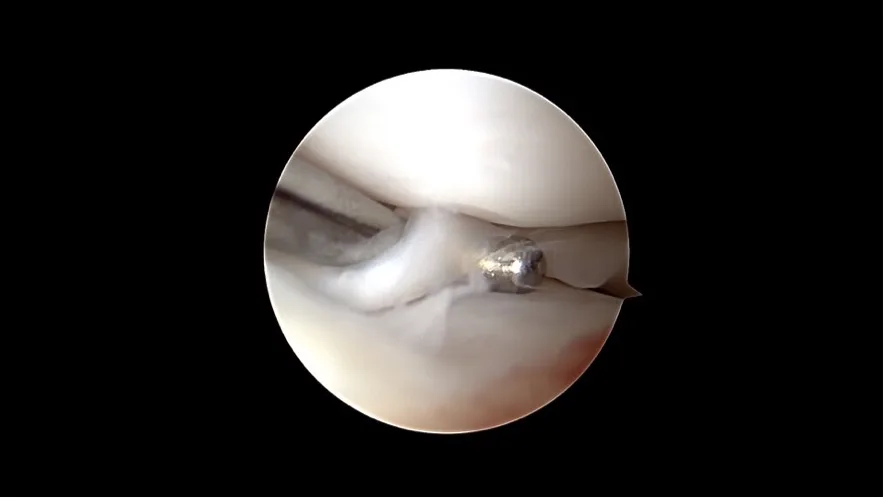

Arthroskopie: Diese Technik ermöglicht eine direkte Sicht auf das Gelenkinnere mit Hilfe einer kleinen Kamera. Über nur wenige Millimeter grosse Hautöffnungen lassen sich Veränderungen am Kreuzband sowie begleitende Schäden wie Meniskusrisse erkennen und in vielen Fällen auch direkt behandeln.

Korbhenkel-artiger Meniskus Riss

Nanoskopie: Noch feiner als die Arthroskopie bietet die Nanoskopie die Möglichkeit, mit besonders kleinen Instrumenten und hochauflösender Bildtechnik im Gelenk zu arbeiten. Das Verfahren ist besonders geeignet für kleinere Hunde. Beide Methoden sind minimalinvasiv, verursachen wenig Gewebetrauma und ermöglichen eine schnellere Erholung.